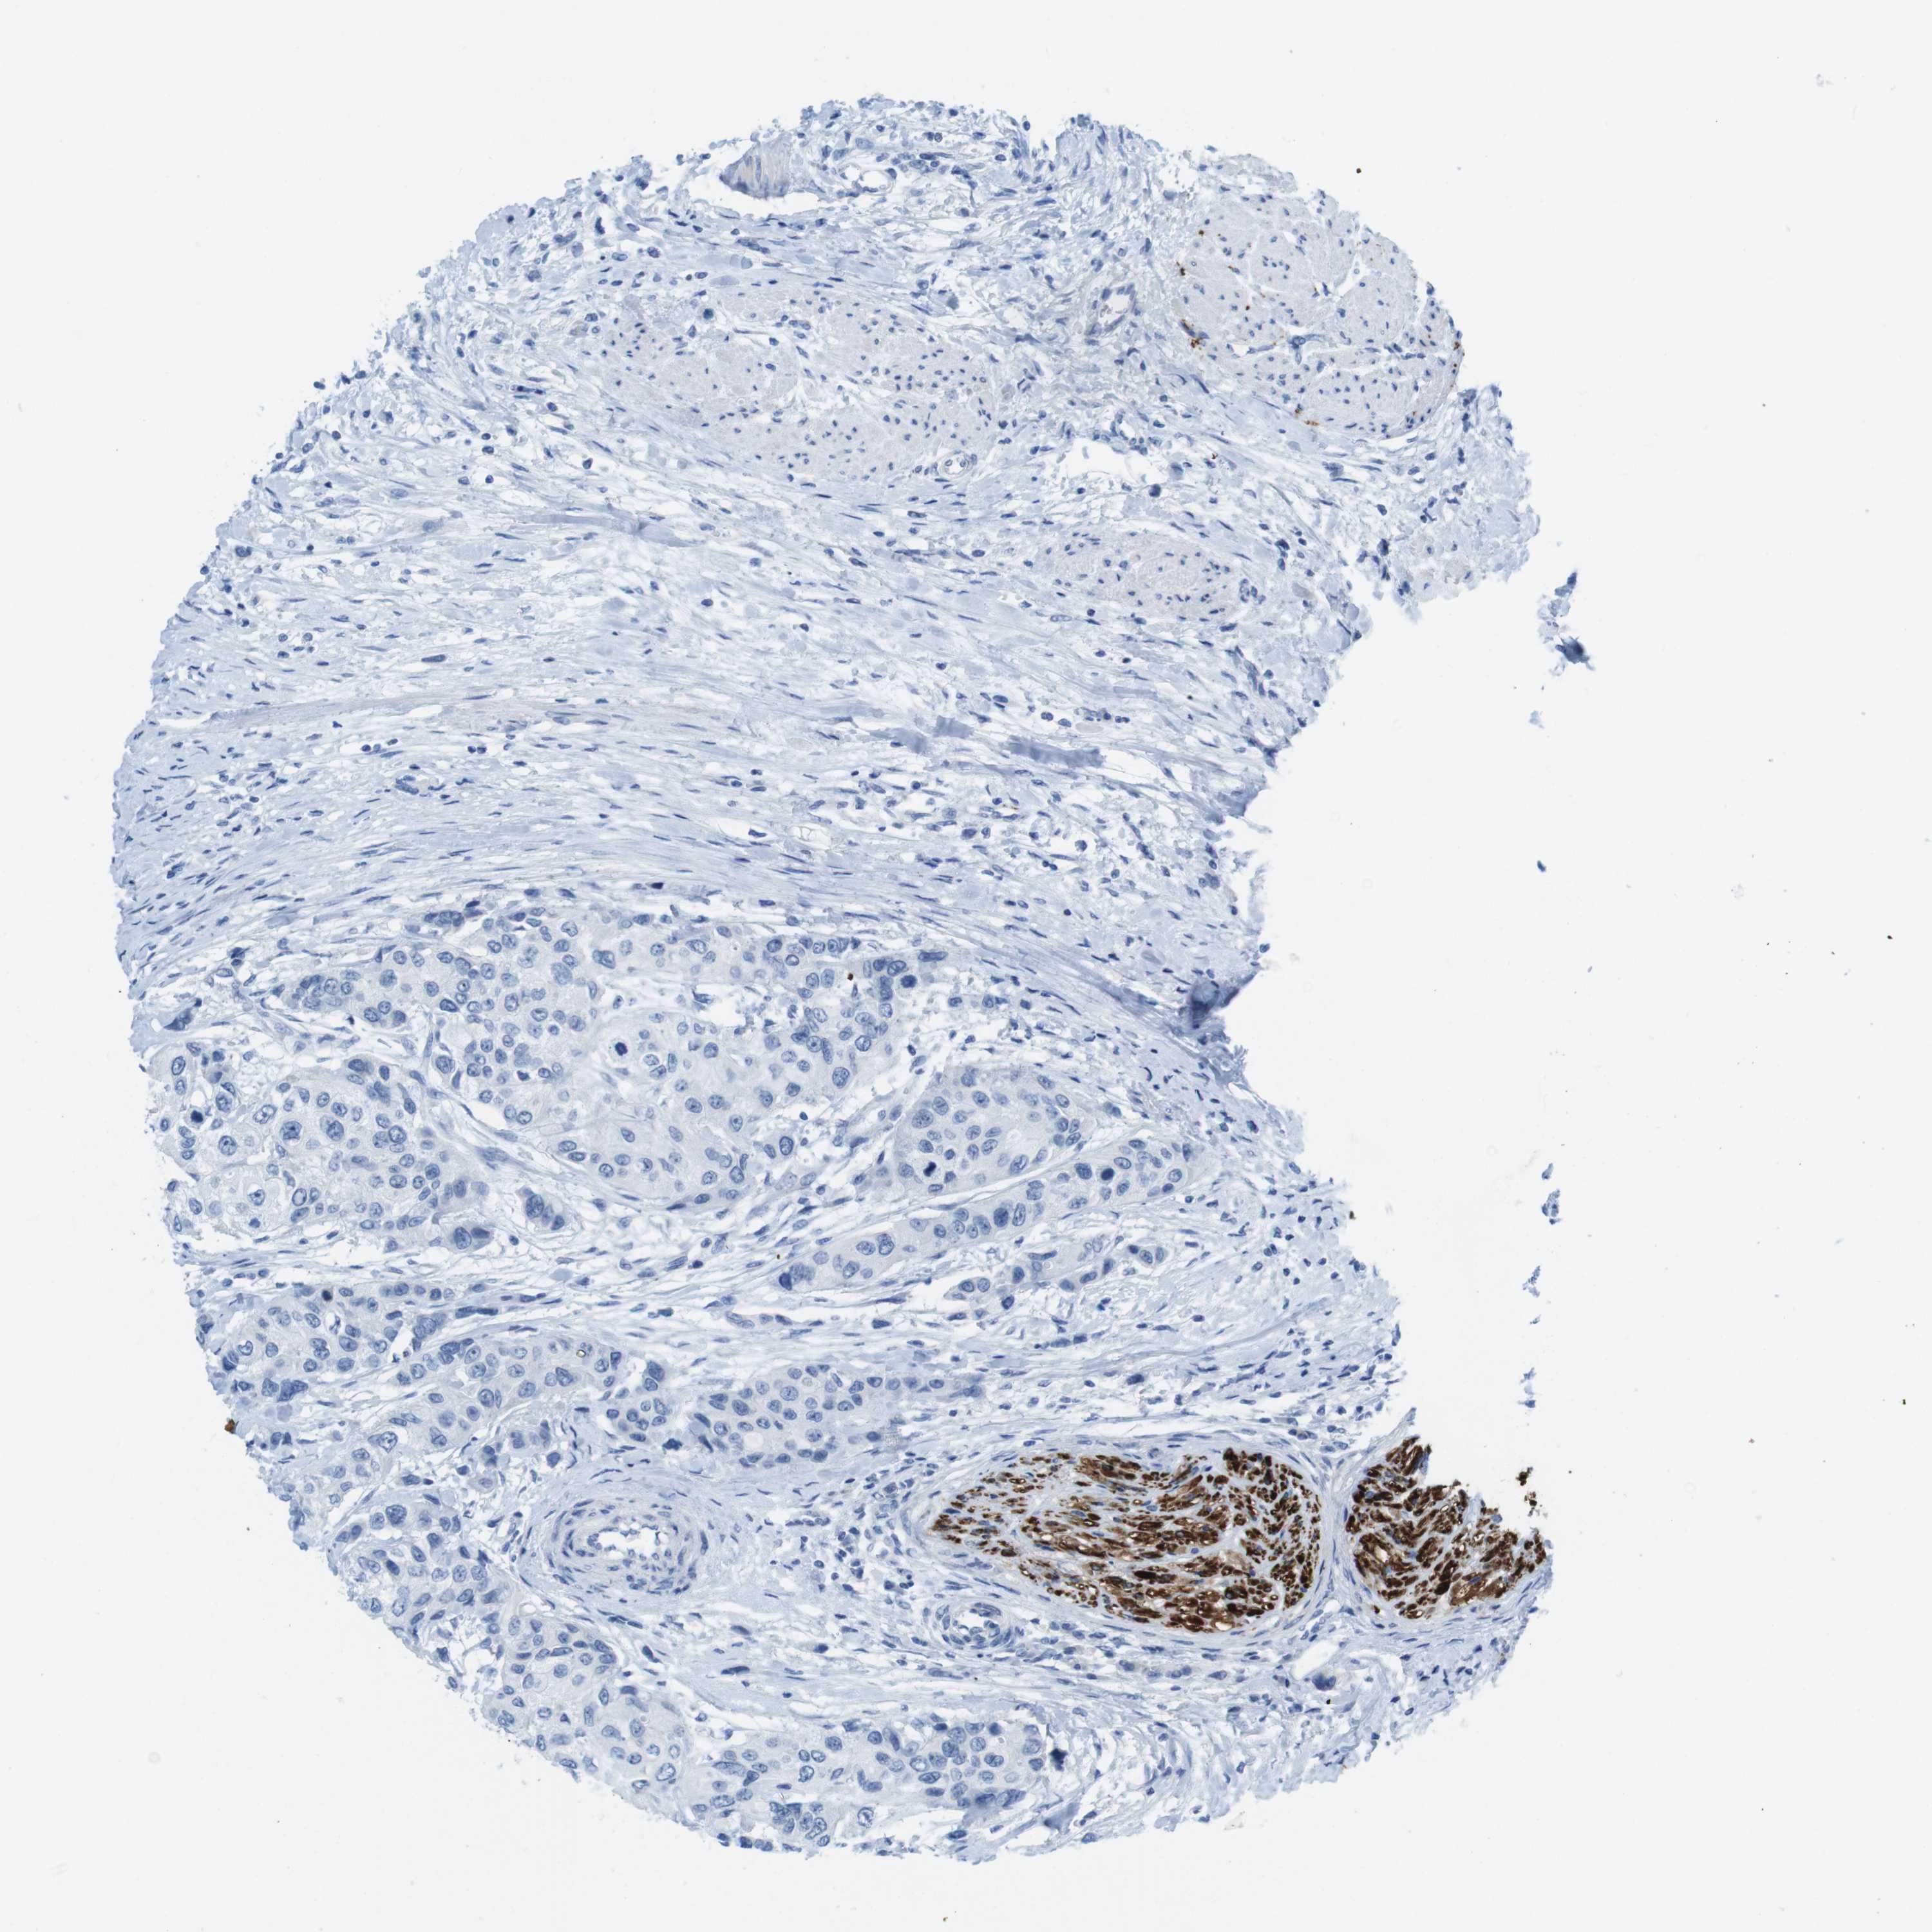

UROTHELIAL CANCER - Protein expressioni

A mouse-over function shows sample information and annotation data. Click on an image to view it in a full screen mode. Samples can be filtered based on level of antibody staining by selecting one or several of the following categories: high, medium, low and not detected. The assay and annotation is described here.

Note that samples used for immunohistochemistry by the Human Protein Atlas do not correspond to samples in the TCGA dataset.

Antibody stainingi

Antibody staining in the annotated cell types in the current human tissue is reported as not detected, low, medium, or high, based on conventional immunohistochemistry profiling in selected tissues. This score is based on the combination of the staining intensity and fraction of stained cells.

Each image is clickable and will lead to virtual microscopy that enables deeper exploration of all samples and also displays staining intensity scores, fraction scores and subcellular localization as well as patient and tissue information for each sample.

Antibody HPA013392

Antibody HPA015600

Antibody CAB004417

Staining

High

Medium

Low

Not detected

Intensity

Strong

Moderate

Weak

Negative

Quantity

>75%

75%-25%

<25%

None

Location

Nuclear

Cytoplasmic/membranous

Cytoplasmic/membranous,nuclear

Urothelial carcinoma, Low grade

Urothelial carcinoma, High grade